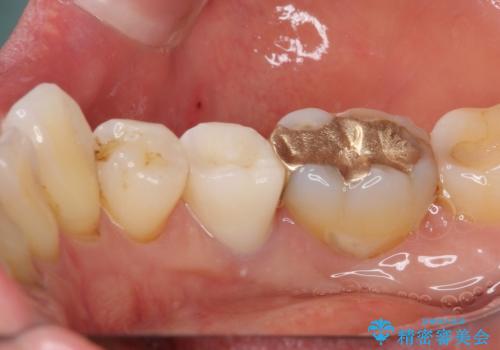

歯に穴があいた 奥歯のセラミック治療

- メインテナンスの際、以前よりものが挟まることが気になっていた患者様です。

神経が取り除かれた歯であるため、虫歯で歯が失われていく際に痛みを伴わなず、気がついたら大きな穴があいていました。

虫歯を全て除去したうえで新しい土台を築製し、セラミッククラウンにより補綴治療を行うこととしました。

虫歯が歯根深くまで及んでいる場合には歯を部分矯正で引っ張り出したり、歯周外科処置が必要となったりしますが、メインテナンスでレントゲン写真を定期的に撮っていたため、幸いにも矯正や外科処置が必要となる前に補綴治療を行うことができました。